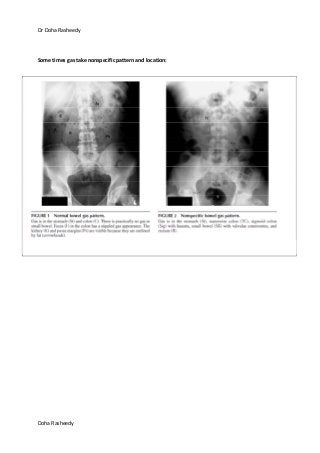

Some times gas take nonspecific pattern and location:

Dr Doha Rasheedy